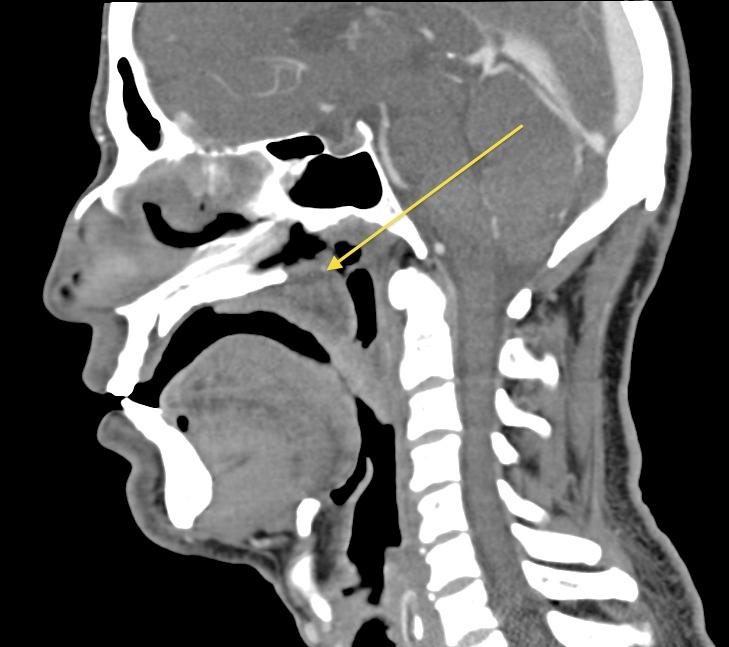

We report a case of a 45-year-old male with severe rhinoscleroma. The patient presented to the emergency room with dyspnea from a long-standing nasal-palatal mass. A tracheostomy was required for airway control. While dyspnea in the presence of an upper airway mass is typical of malignancy, consideration of non-oncological etiologies is important. We review the epidemiology, pathology, diagnosis, and treatment of rhinoscleroma.

我们报告一例45岁患有严重鼻硬结病的男性病例。该患者因长期存在的鼻腭部肿物导致呼吸困难而就诊于急诊室。为控制气道需要进行气管切开术。虽然上气道肿物存在时的呼吸困难是恶性肿瘤的典型表现,但考虑非肿瘤性病因也很重要。我们回顾了鼻硬结病的流行病学、病理学、诊断和治疗。